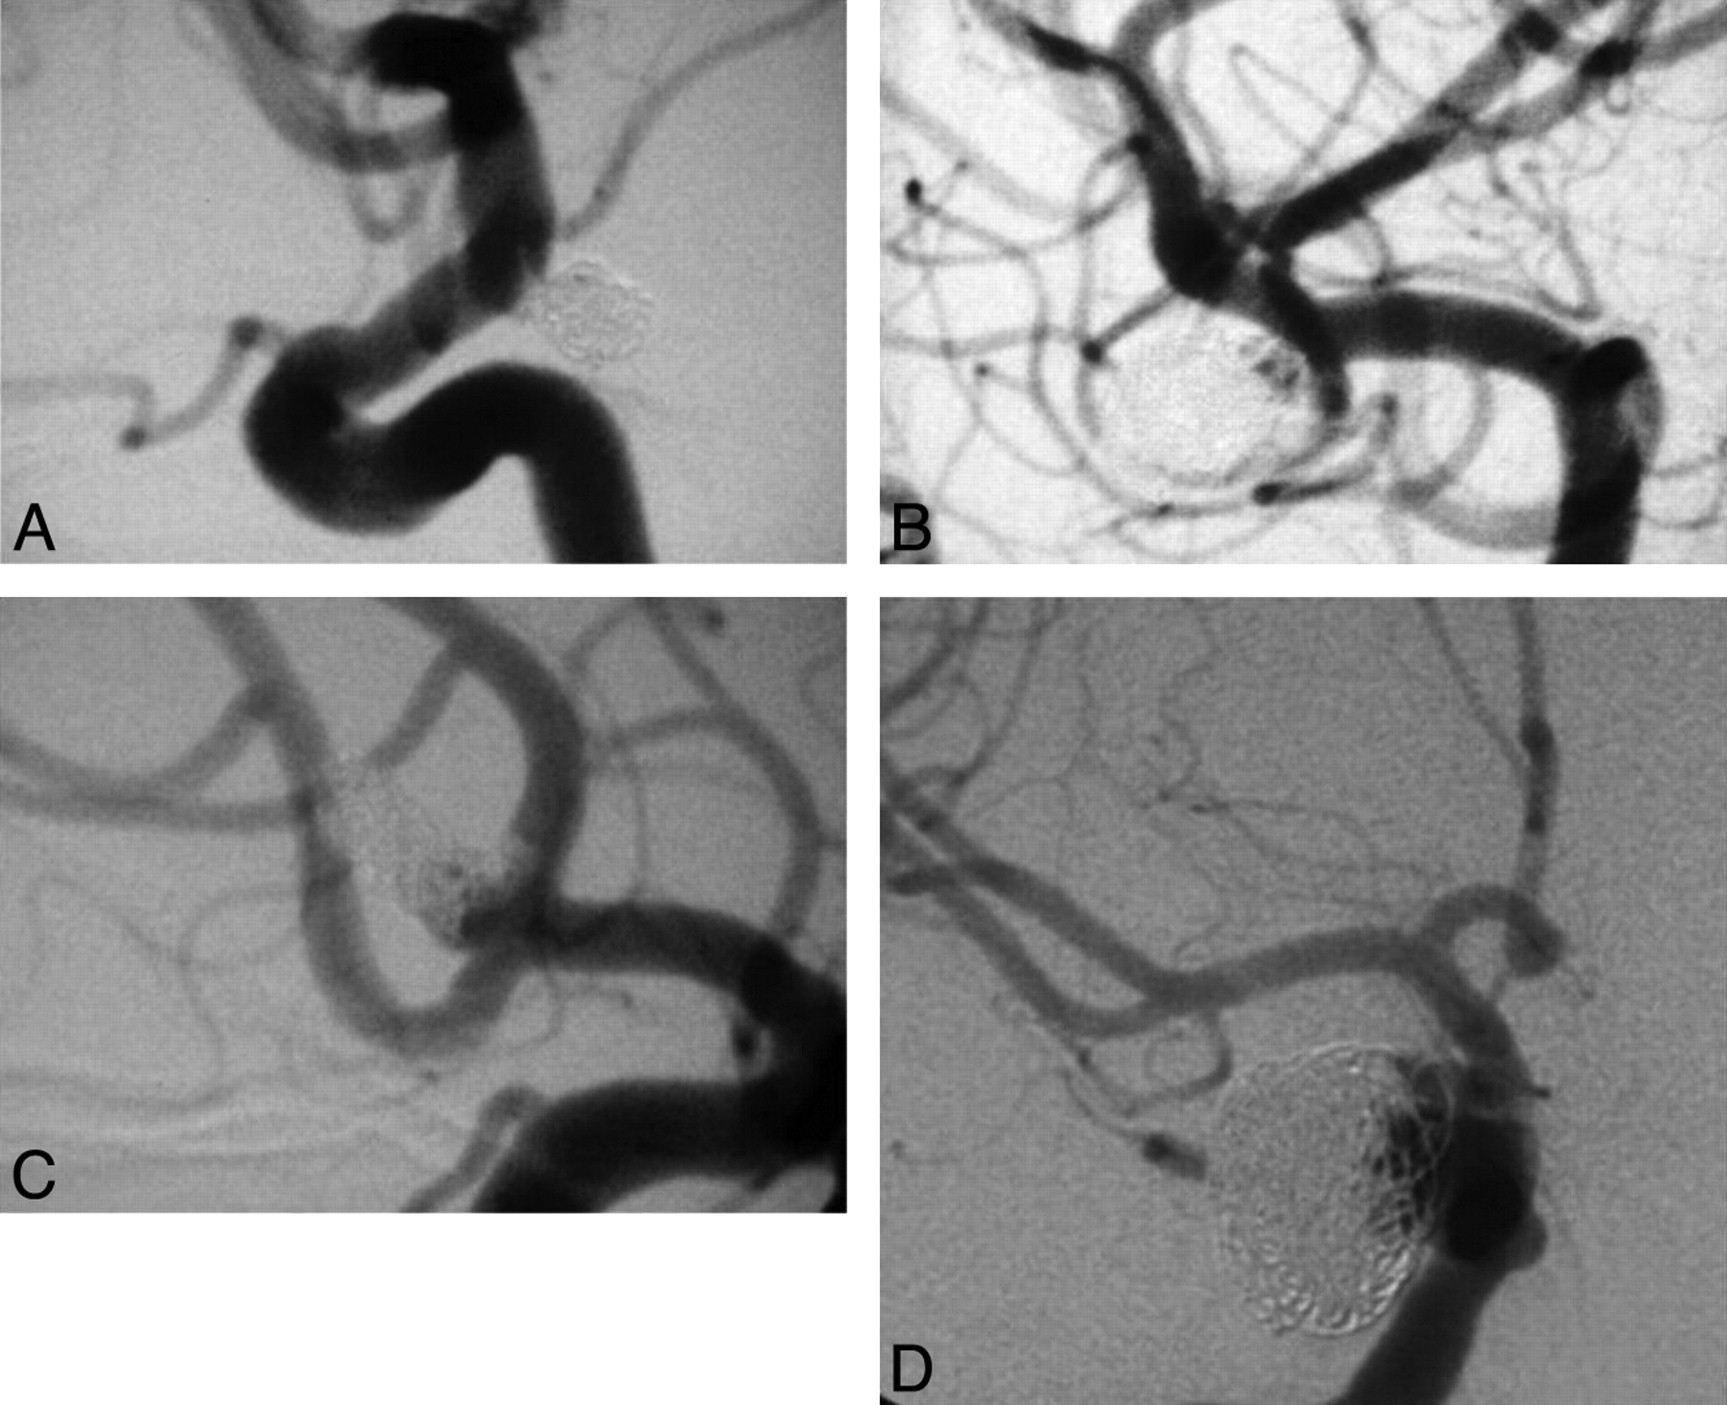

All patients were assigned a rate of occlusion on the immediate postcoiling angiogram at the time of the procedure and again at all subsequent follow-up angiography sessions. The occlusion rate assigned was based on a consensus result from the same 2 experienced interventional neuroradiologists (P.R.B, J.P.T). The occlusion scale used was a modification of the standard Raymond-Roy classification. Class 1 was complete occlusion; Class 2 was divided into 2A and 2B depending on whether the neck remnant was predominantly interstitial, A, or, without coils, B, “the dog ear.” Class 3 was incomplete or residual aneurysm (Fig 1).

Angiographic classification system was a modified Raymond-Roy classification divided into the following groups: complete occlusion (A); neck remnant, interstitial (B); neck remnant with no coils (C); and residual aneurysm (D).